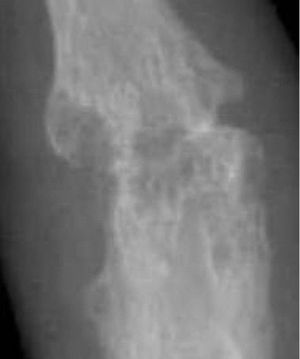

류마티스 관절염이 관절에 미치는 영향을 보여주는 그림

류마티스 관절염을 앓는 고령자의 손 변형(백조 목 변형이라고도 함)

• 변형: 염증이 진행되면서 힘줄 고정, 관절 표면 침식 및 파괴로 인해 운동 범위가 손상되고 변형이 발생한다. 손가락에는 척골 편위, 버튼홀 변형, 백조 목 변형, "Z 엄지" 등 다양한 변형이 나타날 수 있다.[19] 망치 발가락 변형도 나타날 수 있다.[20]